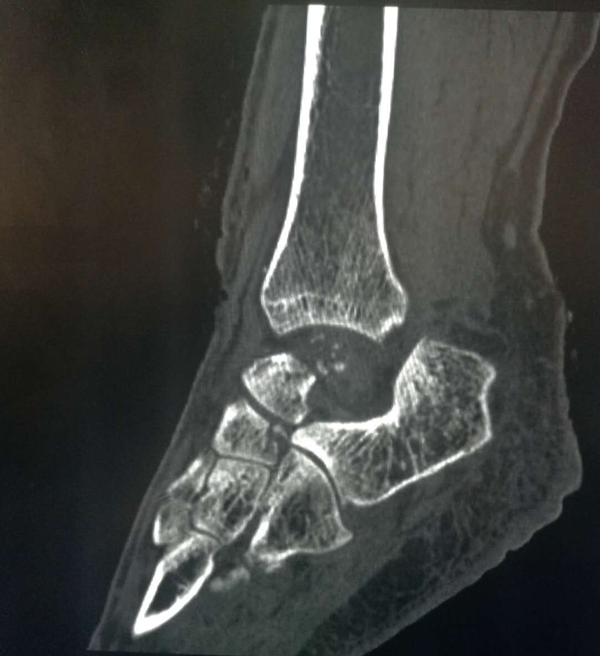

这位43岁的女性患者因不幸遭遇车祸,造成距骨粉碎骨折、脱出,导致左踝关节开放性脱位并距骨体缺损,踝关节活动受限,属罕见的病例。西安高新医院特邀我院骨二科贺西京教授会诊。贺西京教授根据患者病情,结合目前国际先进的3D打印技术,通过诊断,决定采用3D打印定制个体化距骨假体植入方案。由于患者左距骨丢失,贺西京教授团队通过患者右脚CT数据信息,镜像后的三维数字模型为患者“私人定制”量身定做左脚距骨,实施假体置入术,手术由贺西京教授亲自主刀,高新医院骨一科医生配合下,经过两个小时手术,成功将3D打印好的距骨精确无误的植入患者缺失部位,手术获得成功。